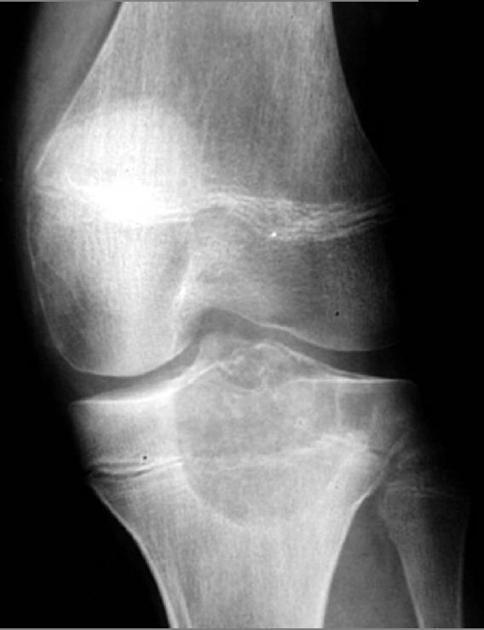

Diagnosis?

Rheumatoid arthritis.